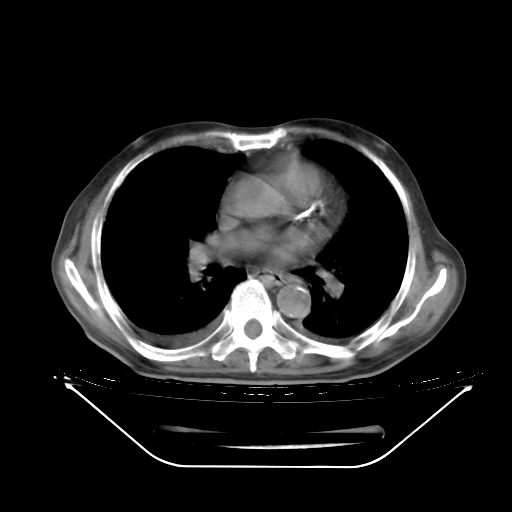

今天复查肺部CT,发现双肺广泛磨玻璃样改变。所以我把3月19日和5月9日相隔50天的肺部CT上传。请大家会诊。

2009年3月19日肺部CT片。

5月9日肺部CT(在4月27日齐鲁医院肺部CT描述部分肺组织磨玻璃样改变,12天后肺组织广泛磨玻璃样改变)

大致读了系列胸部CT:纵隔窗无明显异常,肺窗:从4、27至今:主要是双肺中下野外带可见毛玻璃样改变,目前处于急性肺泡炎阶段,至于原因考虑1、结替组织或胶原血管性疾病所致?2、恶性疾病如恶组在肺部所致的表现或细支气管肺泡癌?3、药物或其它原因如肺蛋白沉着症所致肺泡炎目前不太可能?总之,明天就去请我院的呼吸科、感染科、血液科和临免专家会诊哈。